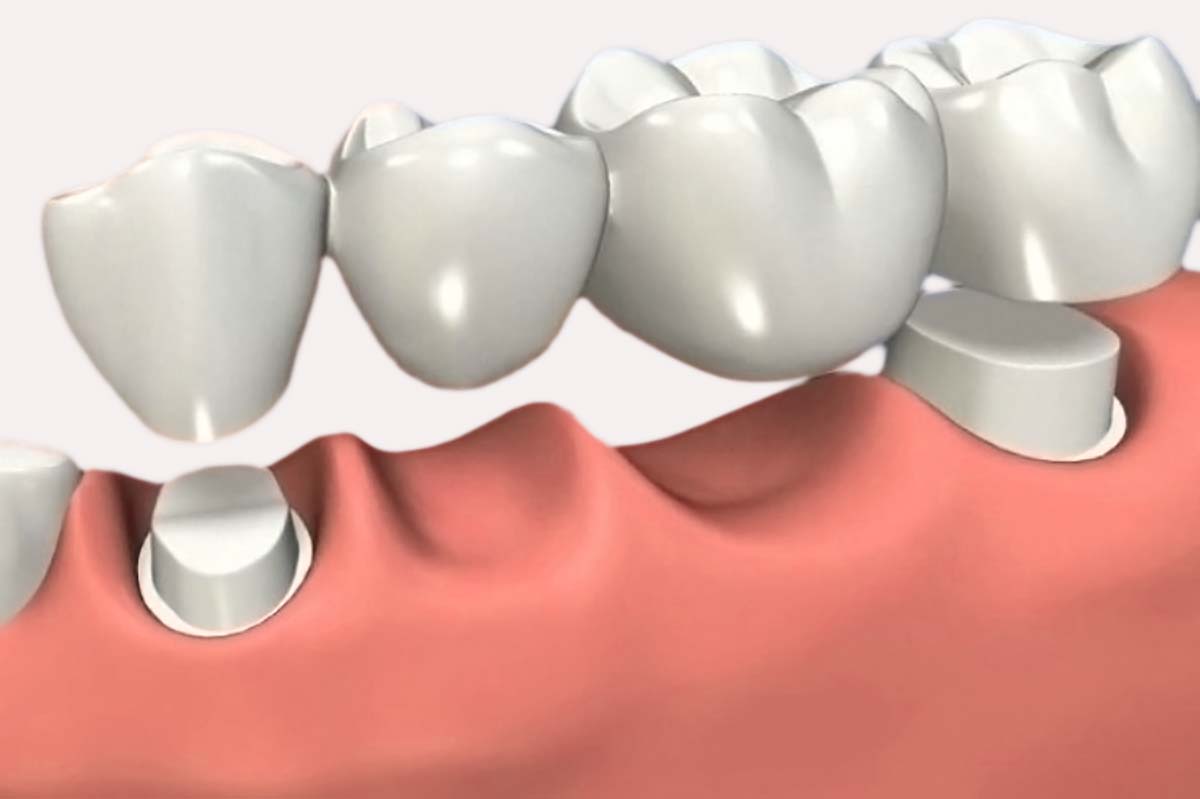

Así mismo hacemos de

conocimiento que "queremos mejorar la calidad de vida de las personas que lo

necesiten, con la realización de tratamientos dentales como coronas, implantes

dentales, dentaduras y diseños de sonrisa entre otros"